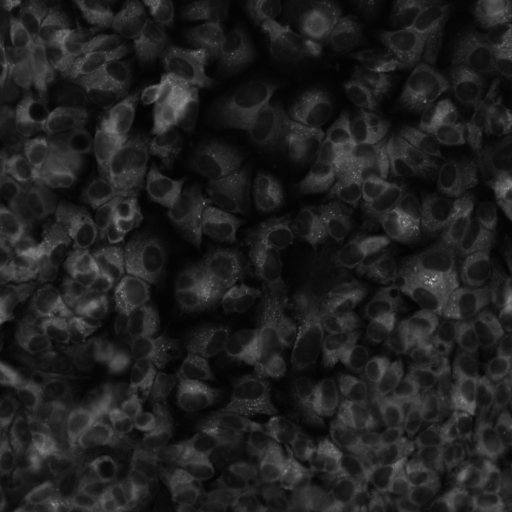

Create an imaging atlas

Access large collections of images; query, download, iterate through images with standardized metadata.